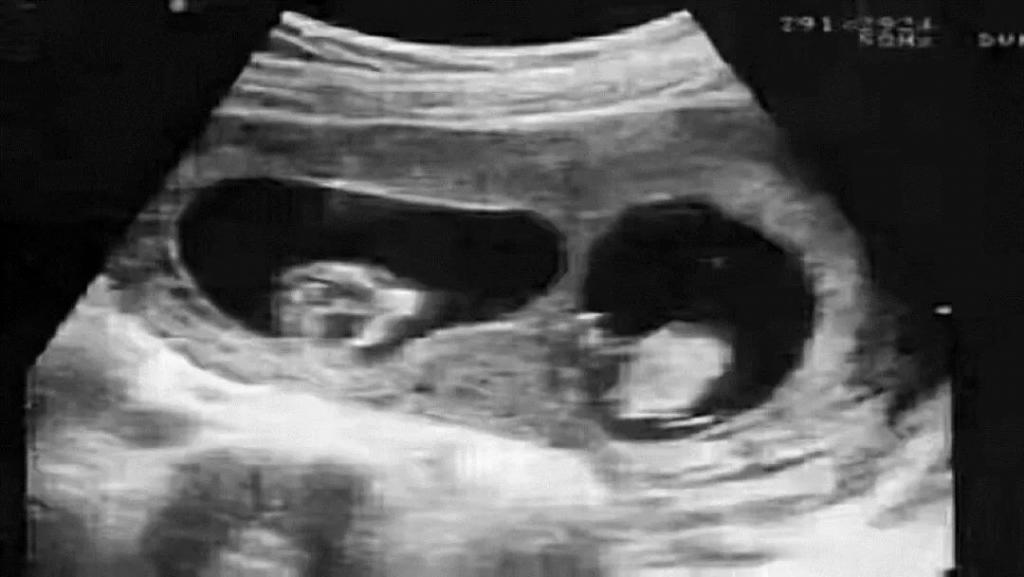

小李和小黄结婚多年,但始终没有成功怀上宝宝。随着年龄越来越大,最终选择了做试管婴儿。可喜的是这次倒是成功了。生下来个大胖小子,全家也很欢喜。

广医三院法医物证司鉴所马晓燕:这可能就遇到了鉴定行业中非常罕见的嵌合体案例,也就是说,这位“爸爸”身体内携带有两个人的 DNA,可能他在妈妈肚子里的时候,还有一个双胞胎弟弟,但是这个双胞胎弟弟的胚胎没有发育下来,反而和他的胚胎出现了融合,导致这个“爸爸”携带两个人的 DNA 出生,而且他把弟弟的 DNA 传给了孩子。

嵌合体其实也称为“奇美拉”现象。奇美拉原本指的是希腊神话中,一种狮头,羊身蛇尾的怪物,可以参考中国的四不像。而嵌合体正是一个人的体内含有多组 DNA 的现象,也可以通俗的理解为两个受精卵融合成一颗的现象。科学家认为这个发作概率大概在 10%-15%。

第一种就是和上文的事例一样,属于双胞胎在发育过程中,另一个抢不过对方,从而导致被“吞噬融合”,只能留下一部分 DNA 了。不过这也不要觉得残忍,算是生命的一种优胜劣汰吧,毕竟双胞胎原本对营养、空间等方面有更多需求,属于是无意识的行为吧,当然这是比较少见的情况。毕竟全世界这种被报道出来的,不超过 100 例。